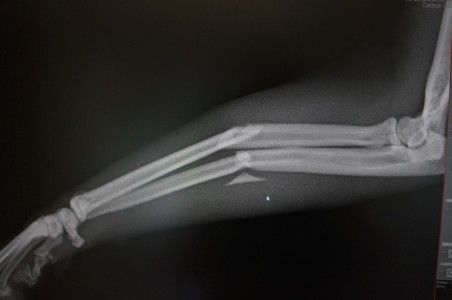

Digitales Röntgen

- allgemeine Aufnahmen

- Frakturbehandlung